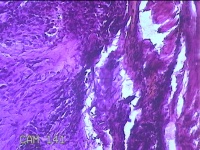

右侧中指尺侧包块

性别

女

年龄

53岁

临床诊断

肌腱腱鞘囊肿

一般病史

发现右侧中指尺侧一包块1年余,无明显疼痛及不适。

标本名称

大体所见

灰白暗红色肿物1.2x0.8x0.3cm一个,表面糜烂,切面灰白粉红色,质软。